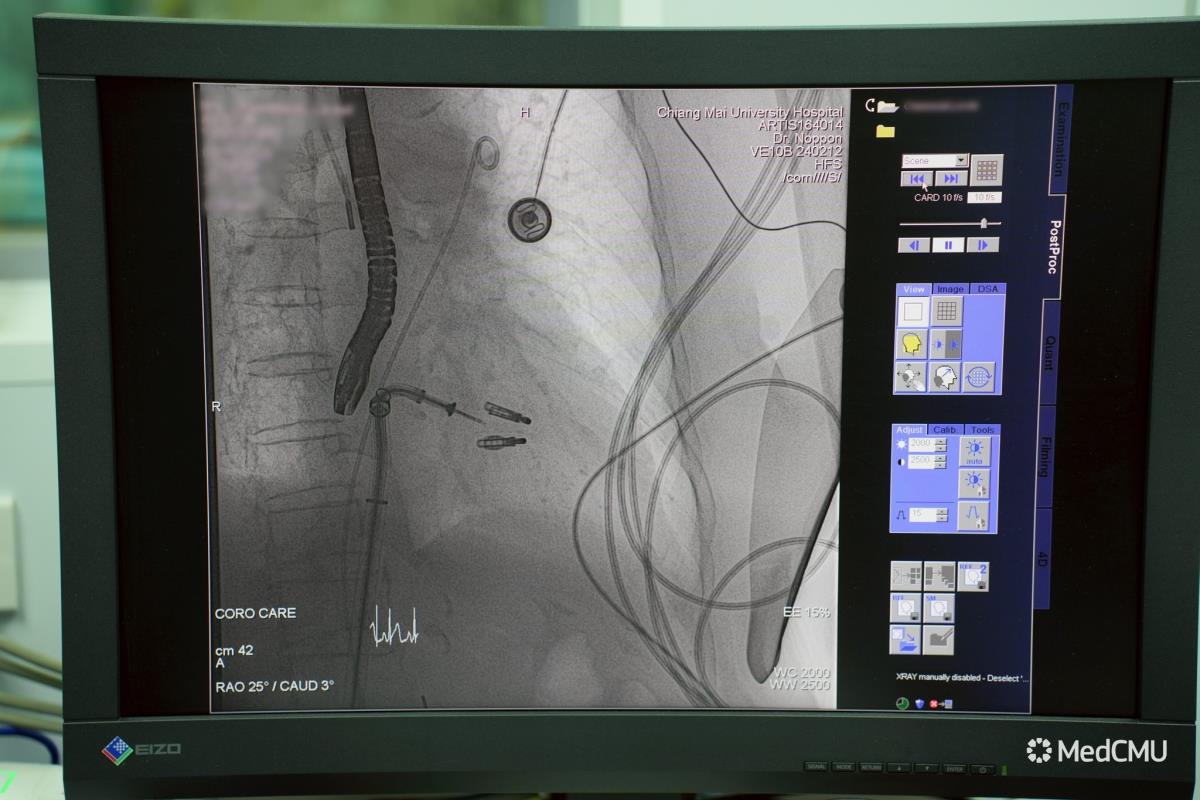

คณะแพทยศาสตร์ มหาวิทยาลัยเชียงใหม่ ประสบความสำเร็จในการรักษาผู้ป่วยโรคลิ้นหัวใจไมตรัลรั่ว (Mitral Regurgitation) ด้วยเทคนิค Edge-to-Edge Transcatheter Repair (MitraClip) โดยไม่ต้องผ่าตัดเปิดหน้าอก นับเป็นเคสแรกของภาคเหนือ ซึ่งนับเป็นนวัตกรรมการซ่อมแซมลิ้นหัวใจรูปแบบใหม่ ช่วยให้ผู้ป่วยฟื้นตัวเร็ว เจ็บน้อย และกลับบ้านได้ภายในเพียง 1-2 วัน

เทคนิค MitraClip เป็นนวัตกรรมการรักษาที่ใช้คลิปขนาดเล็กหนีบลิ้นหัวใจไมตรัลทั้งสองด้านให้ปิดแนบกัน โดยสอดคลิปผ่านสายสวนจากหลอดเลือดดำบริเวณขาหนีบ แทนการผ่าตัดเปิดหน้าอก วิธีนี้ช่วยให้เลือดไม่ไหลย้อนกลับ ลดภาระการทำงานของหัวใจ และผู้ป่วยสามารถฟื้นตัวได้รวดเร็วโดยไม่ต้องใช้เครื่องหัวใจและปอดเทียม

สำหรับเคสแรกนี้ เป็นผู้ป่วยหญิงอายุ 85 ปี มีภาวะหัวใจวายเฉียบพลันและต้องใส่ท่อช่วยหายใจกว่า 10 วัน เนื่องจากเส้นเอ็นยึดลิ้นหัวใจฉีกขาด ส่งผลให้ลิ้นหัวใจรั่วอย่างรุนแรง ซึ่งด้วยอายุและโรคร่วมหลายโรค ผู้ป่วยรายนี้ไม่เหมาะกับการผ่าตัดใหญ่ ทีมแพทย์หัวใจโรงพยาบาลมหาราชนครเชียงใหม่จึงตัดสินใจใช้เทคนิค MitraClip แทนการผ่าตัดเปิดหน้าอก

การรักษาใช้เวลาประมาณ 2–3 ชั่วโมง โดยใส่คลิปเพียง 2 ตัว หลังหัตถการ ผู้ป่วยสามารถถอดท่อช่วยหายใจได้ในวันถัดมา อาการเหนื่อยลดลงชัดเจน และมีแนวโน้มกลับบ้านได้ภายใน 1 สัปดาห์

เทคนิค MitraClip ได้รับการยอมรับและใช้กันอย่างแพร่หลายทั่วโลกมากว่า 15 ปี โดยให้ผลการรักษาใกล้เคียงกับการผ่าตัดในผู้ป่วยที่เหมาะสม ปัจจุบันในประเทศไทยมีเพียงไม่กี่ศูนย์ที่สามารถทำหัตถการนี้ได้ เนื่องจากต้องอาศัยทีมแพทย์เฉพาะทาง เครื่องมือขั้นสูง และความชำนาญในการทำอัลตราซาวนด์หัวใจผ่านหลอดอาหารเพื่อใช้เป็น “ดวงตานำทาง” ระหว่างทำหัตถการ